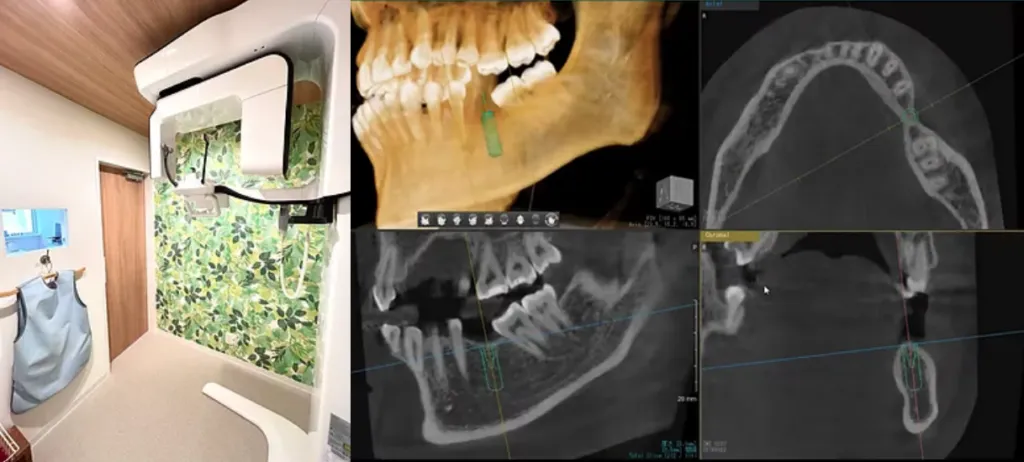

CT・パノラマレントゲン

歯科用CTは3次元の精密な診査・診断ができ、インプラントや根管治療などの高度な治療をより的確に行うことに役立ちます。デジタルパノラマレントゲンはハイスピード撮影により、従来のレントゲンに比べ被ばく量を約1/7に削減しています。